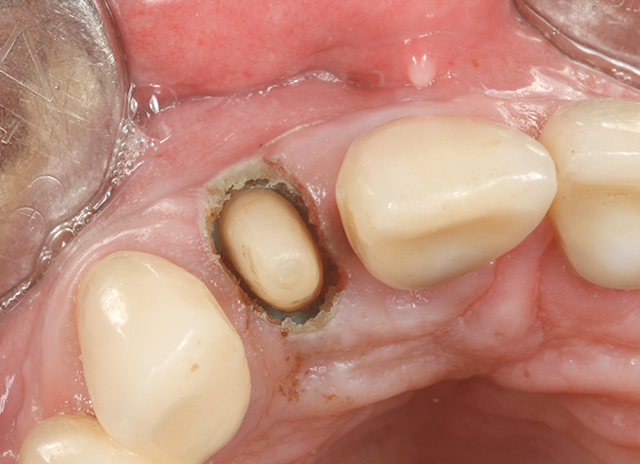

Exposing the root makes it possible to do a preparation and a core build up. Shortly after the use of XO Odontosurge.

Easy removal of the soft tissue. There is little or no bleeding from the tissue.

Core build up is finished. Dry conditions suitable for impression even deep subgingivally.